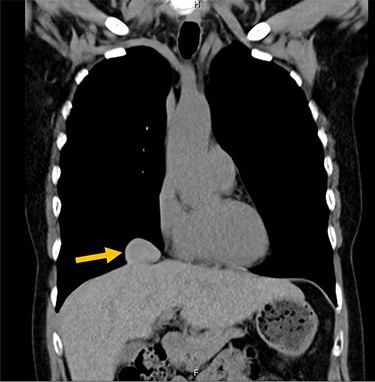

A 54-year-old female without prior thoraco-abdominal trauma presented to the office with two right lower lobe lung nodules. The nodules were initially noted incidentally on a computerized tomography (CT) scan in August 2009 and measured 1.5 cm × 2.8 cm and 0.9 cm × 1.3 cm (Figs 1 and 2). A follow-up CT scan and positron emission tomography (PET) performed in 2010 demonstrated that the nodules were stable in size. The patient was lost to follow-up until March 2019 when she had a CT scan for concern for pneumonia. On these images, the lung nodules had increased in size to 2.8 cm × 4.1 cm and 1.1 cm × 1.4 cm. The patient was otherwise asymptomatic. A PET scan was obtained which showed hypermetabolic nodules with maximum SUV of 3.29 and 1.4, for the larger and smaller nodule, respectively (Figs 3 and 4). Radiographic appearance as well as the growth pattern was consistent with low-grade malignancy suspicious for carcinoid tumor. CT-guided biopsy was not feasible because of location of the tumor.